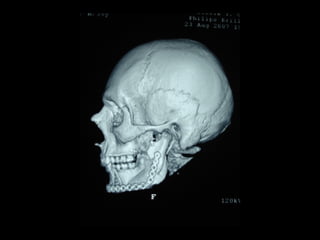

Tomografía computarizada

De seno maxilar corte sagital.

Area de implantación

Dentaria.